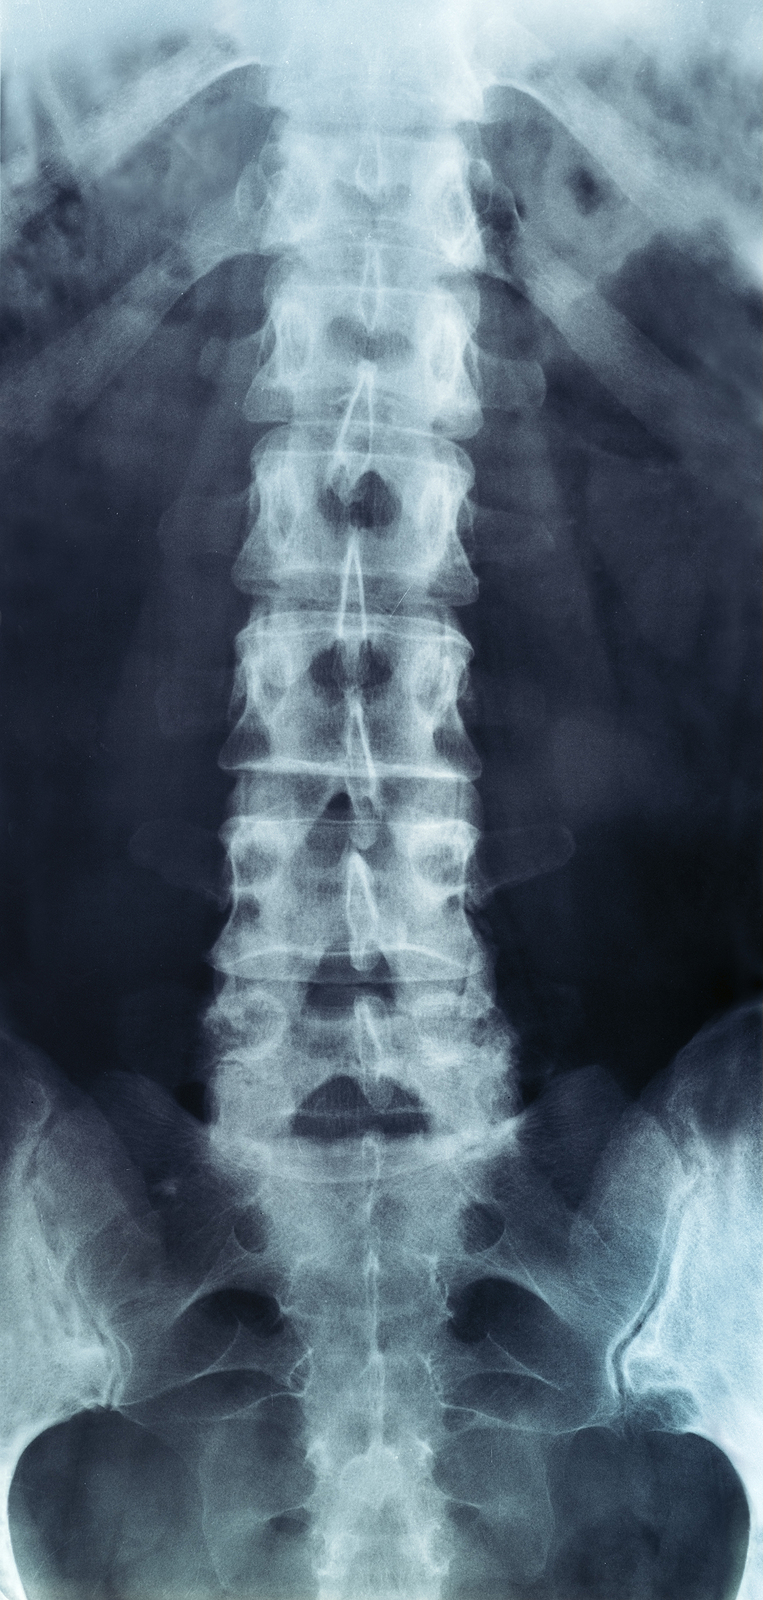

The human spine is made up of 24 spinal bones, called vertebrae, as well as the sacrum and the coccyx. The sacrum is a triangular bone near the bottom of the spine and the coccyx is more commonly known as the tailbone.

Vertebrae are stacked on top of one another to create the spinal column. The spinal column gives the body its form and helps sustain an upright position.

The lumbar spine—where pain is often experienced—is made up of five vertebrae positioned near the bottom of the spinal column. Doctors often refer to these vertebrae as levels L1, L2, L3, L4 and L5. The ‘L’ refers to ‘lumbar’. The lowest vertebra, L5, is connected to the top of the sacrum—a triangular bone at the base of the spine that is located between the two pelvic bones. Some people are born with an extra or sixth lumbar vertebra called L6. Having an extra vertebra doesn't usually cause physical problems.

Most people with low back pain will NOT need x-rays or other tests to diagnose and treat their pain. In some cases, if an x-ray or other diagnostic could be helpful, your physical therapist will refer you to a doctor for further diagnostic imaging.

If diagnostic tests are deemed necessary, there are several different tests that your doctor may recommend. Radiological imaging tests allow your doctor to see the anatomy of your spine, which assists the determination of what may be causing your back pain. Knowing what structures may be contributing to your back pain may help further direct the most appropriate treatment to assist you.

X-rays

X-rays are usually the first test ordered before any of the more specialized tests are completed. X-rays use electromagnetic radiation to show problems with bones and can also reveal problems such as fractures, infections, or bone tumors. X-rays of the spine can give your doctor information about bone alignment and can demonstrate how much degeneration has occurred in the spine. Both alignment and degeneration can affect the amount of space in the neural foramina and between the discs, which subsequently impacts the nerves in the area. This is important information your health care professional can use to establish a treatment plan.